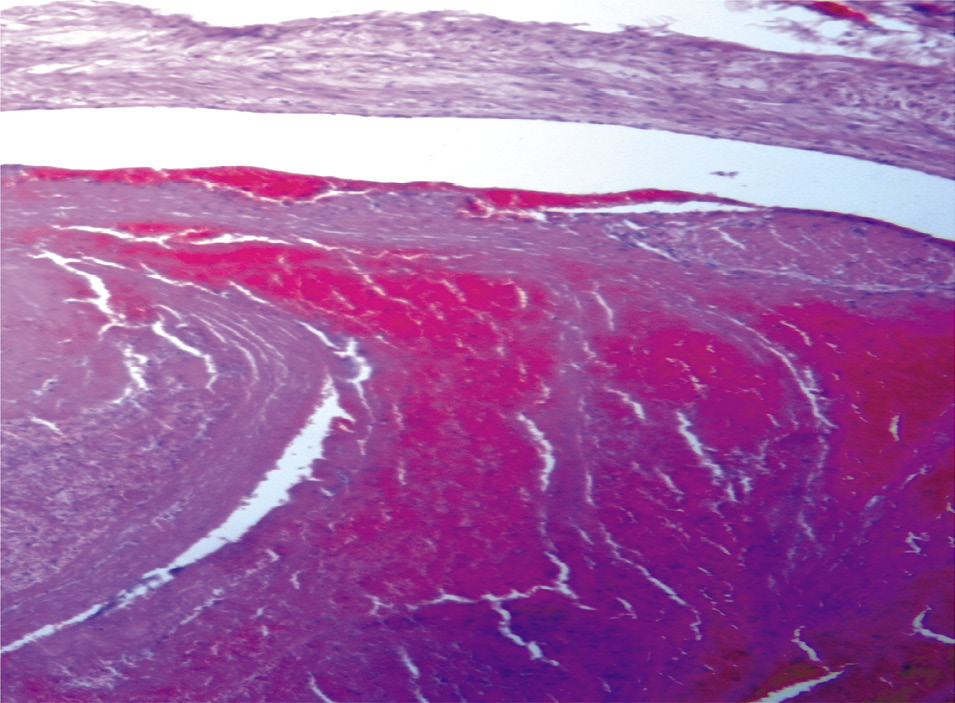

При секционном исследовании определяются признаки, характерные для периферического рака правого легкого с множественными метастазами по всем полям легких, в печень, селезенку, поджелудочную железу, с отсутствием метастазов в лимфатические узлы. При макроскопическом исследовании структура легких просматривается с трудом из-за выраженного диссеминированного наличия серых плотноватых узлов в диаметре от 0,2 до 0,9 см, местами сливающихся. В области средней доли правого легкого определяется опухолевая ткань с выраженным слиянием и тенденцией формирования конгломерата, распространяясь к долевому бронху, без сужения просвета. При гистологическом исследовании отмечаются обширные участки формирования опухолевой ткани, состоящей из солидных структур с железистой дифференцировкой опухолевой ткани разной величины и формы, выстланные крупными приз- матическими клетками с округлыми и овальными базально расположенными ядрами, цитоплазма которых хорошо выражена. Отмечается выраженный полиморфизм клеток с большим числом патологических митозов (рис. 1, 2). В просвете сегментарных и мелких ветвей легочной артерии – свертки крови, тромбы в диаметре от 0,2 до 0,7 см, длиной до 3,0 см, выдавливающиеся в виде «червячков» (рис. 3).

Рис. 1. Микроскопическая картина аденокарциномы в легких, состоящей из полиморфных клеток с атипичными гиперхромными ядрами, с инфильтрирующим ростом и распадом. Окраска гематоксилином и эозином, ×900.